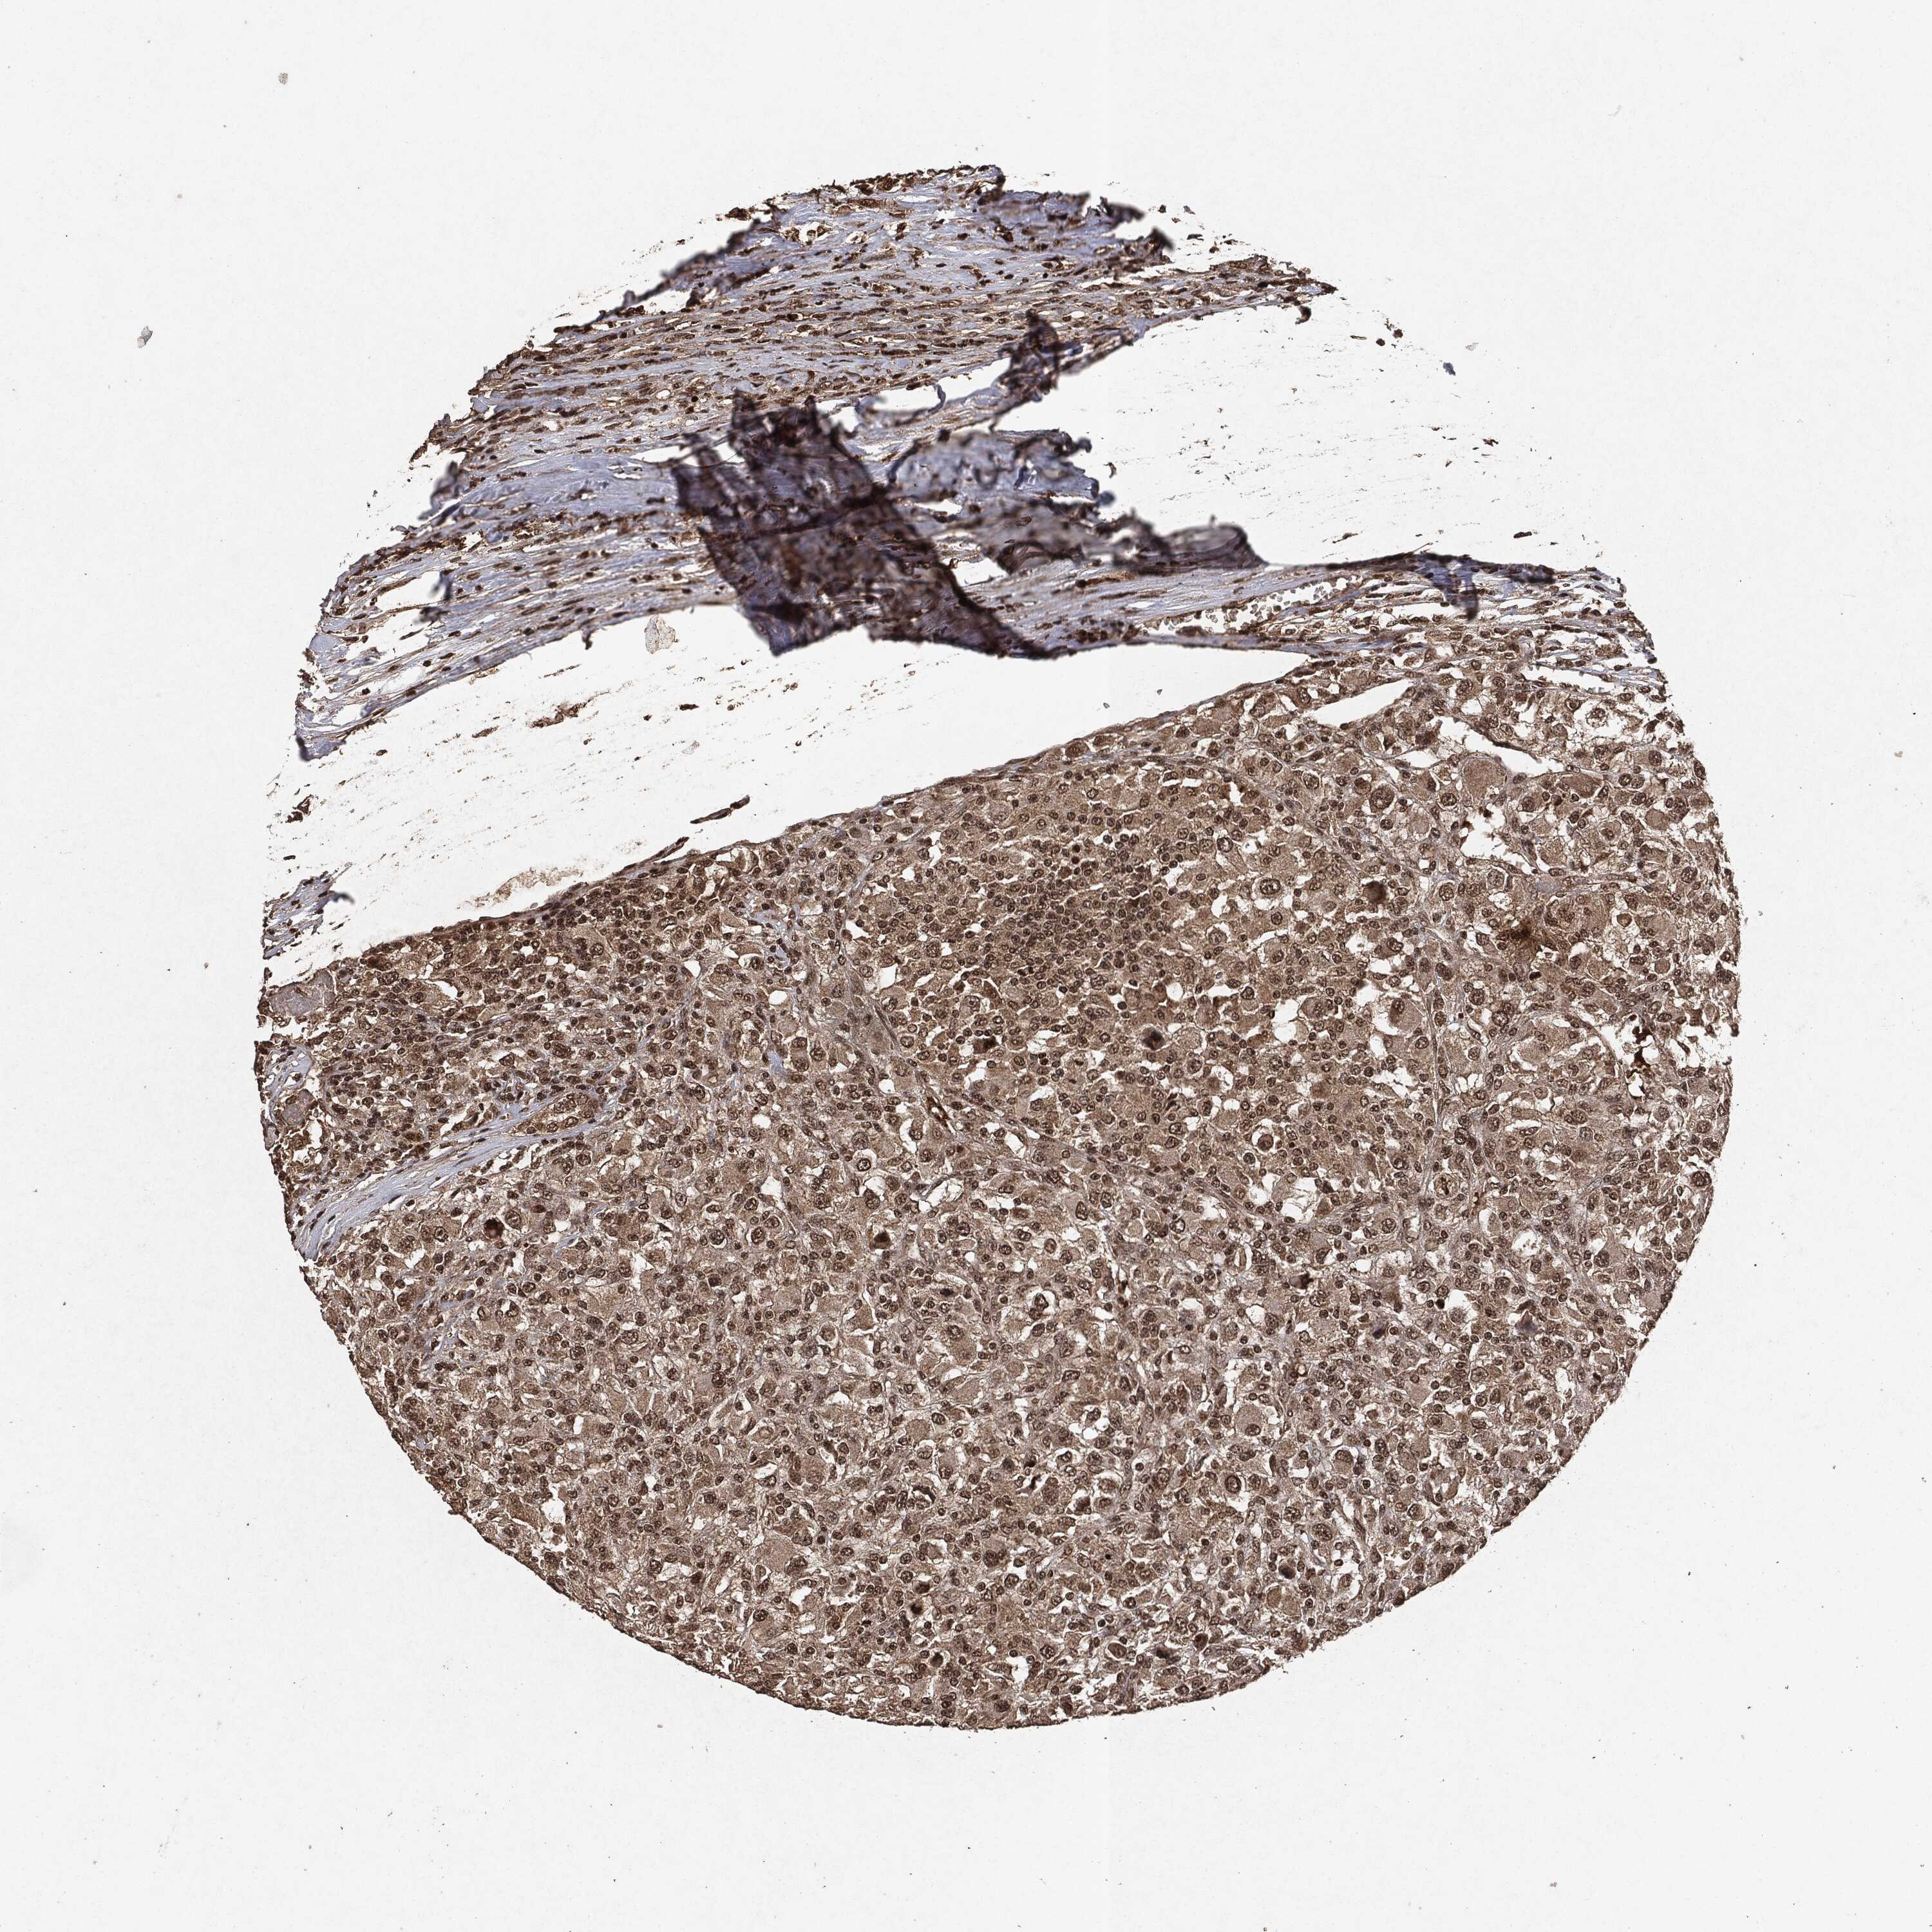

KIDNEY RENAL PAPILLARY CELL CARCINOMA (TCGA) - Interactive survival scatter ploti

The Survival Scatter plot shows the clinical status (i.e. dead or alive) for all individuals in the patient cohort, based on the same data that underlies the corresponding Kaplan-Meier plots. Patients that are alive at last time for follow-up are shown in blue and patients who have died during the study are shown in red.

The x-axis shows the expression levels (FPKM) of the investigated gene in the tumor tissue at the time of diagnosis. The y-axis shows the follow-up time after diagnosis (years). Both axes are complimented with kernel density curves demonstrating the data density over the axes. The top density plot shows the expression levels (FPKM) distribution among dead (red) and alive patients (blue). The right density plot shows the data density of the survived years of dead patients with high and low expression levels respectively, stratified using the cutoff indicated by the vertical dashed line through the Survival Scatter plot. This cutoff is automatically defined based on the FPKM cutoff that minimizes the p-score. The cutoff can be changed by dragging the vertical line or by entering a cutoff value in the square labeled "Current cut-off".

Under the Survival Scatter plot the p-score landscape (black curve; left axis) is shown together with dead median separation (red curve; right axis). Dead median separation is the difference in median mRNA expression between patients who have died with high and low expression, respectively. It is calculated as follows: median FPKM expression of dead patients with high expression - median FPKM expression of dead patients with low expression. This is intended to aid the user in visually exploring custom cutoffs and the associated p-scores and dead median separation.

Individual patient data is displayed and can be filtered by clicking on one or more of the category buttons on the top of the page. Categories describing expression level and patient information include: high, low, alive, dead, female, male and tumor stages. The scale of the x-axis can be toggled between linear and log-scale by clicking on the "x log" button. Mouse-over function shows TCGA ID, patient information and mRNA expression (FPKM) for each patient.

& Survival analysisi

Kaplan-Meier plots summarize results from analysis of correlation between mRNA expression level and patient survival. Patients were divided based on level of expression into one of the two groups "low" (under cut off) or "high" (over cut off). X-axis shows time for survival (years) and y-axis shows the probability of survival, where 1.0 corresponds to 100 percent.

EGFR is not prognostic in Kidney Renal Papillary Cell Carcinoma (TCGA)